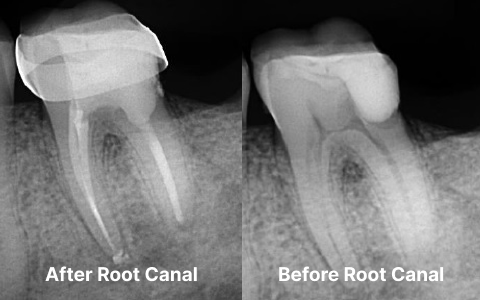

The procedure starts with removing the infected or damaged pulp from the tooth. The root canals are then carefully cleaned, disinfected, and filled to prevent further infection. Once the treatment is completed, a crown or filling is placed to protect the tooth and restore its natural appearance.